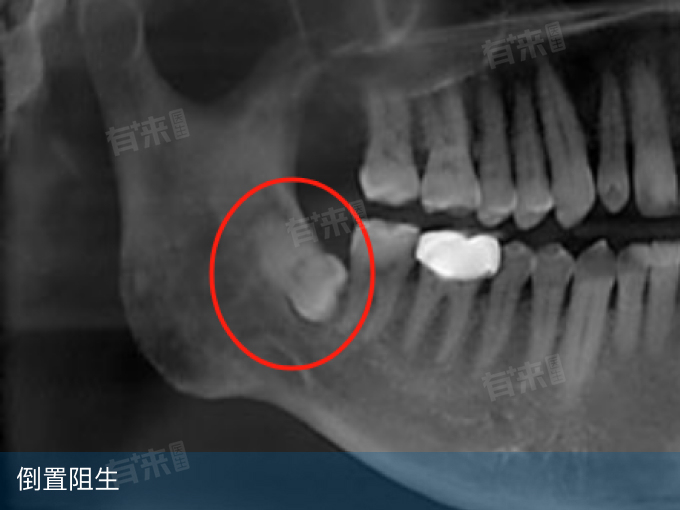

然而,并非所有水平阻生智齿都必须立即拔除。若智齿完全埋于骨内,与邻牙无接触,且无感染史,可定期观察。影像学检查(如全景X光或CBCT)能帮助评估智齿位置及周围结构,辅助决策。对于高龄患者或全身健康状况不佳者,若智齿未引发症状,也可能选择保守处理。